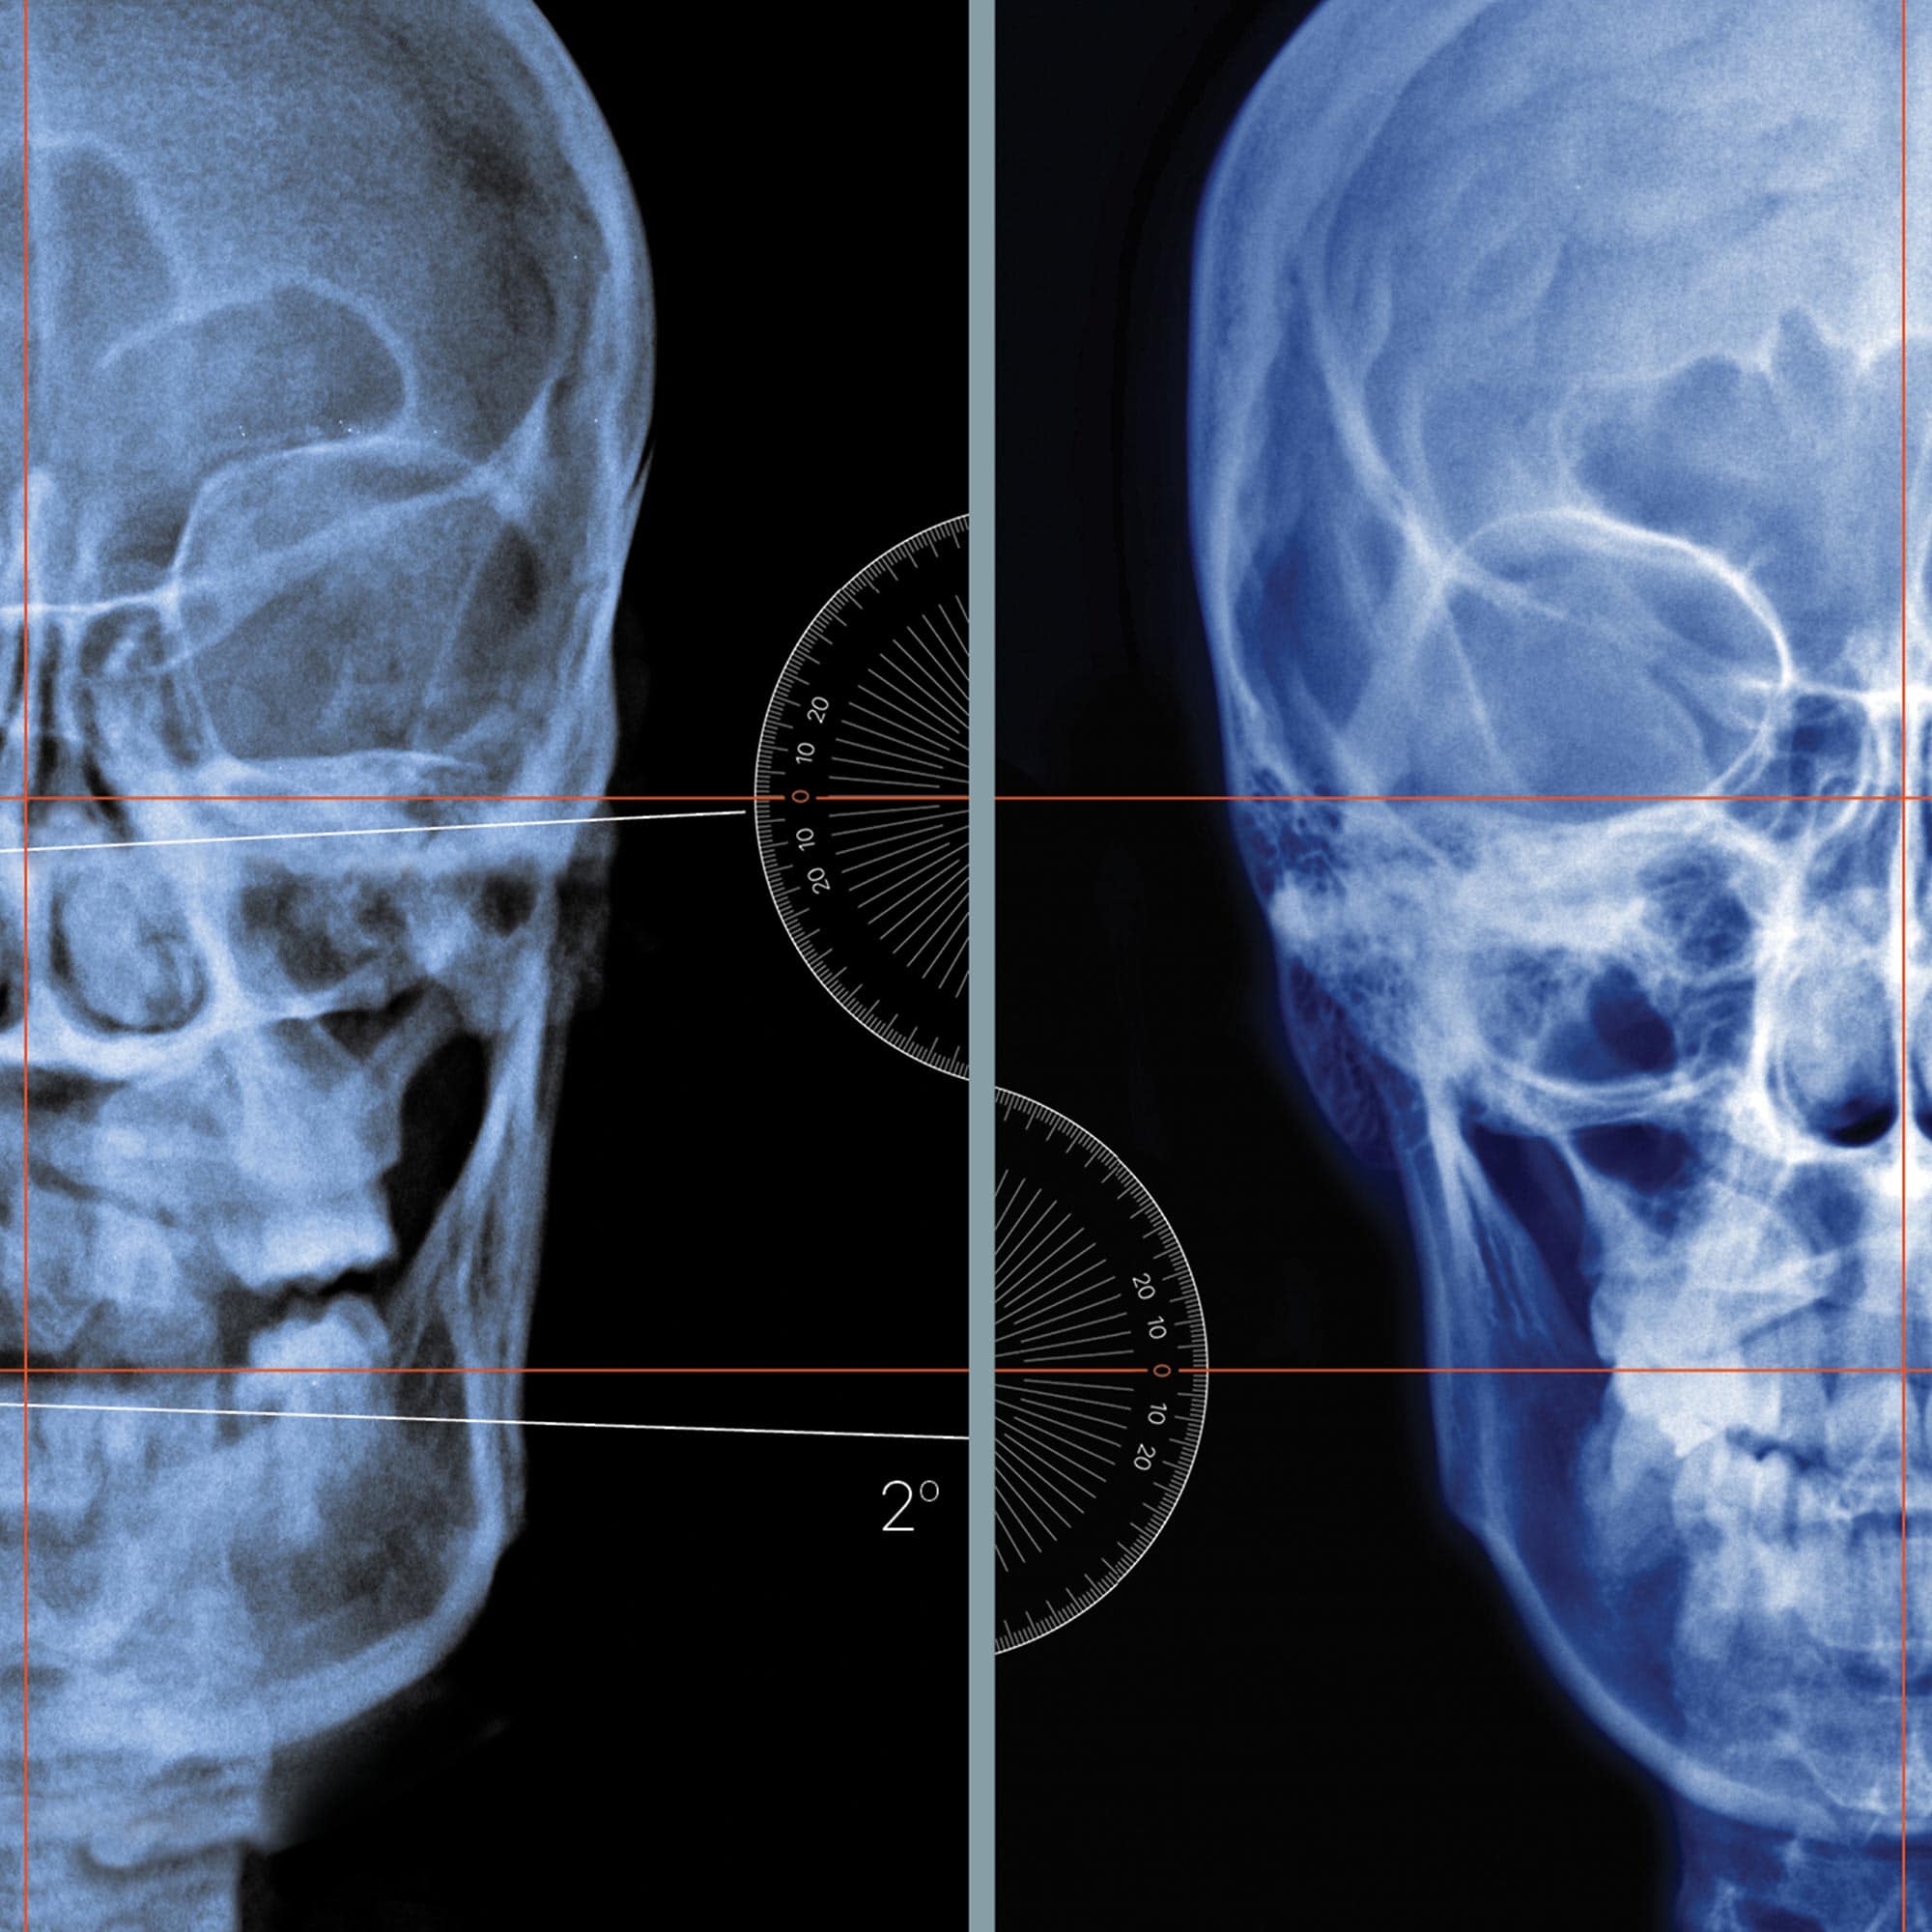

Temporomandibular joint disorder and symptoms.

TMJ disorder is a condition that affects the joints and muscles of the jaw. It can cause pain, discomfort, and difficulty in talking, eating, and even sleeping. Increasing awareness about TMJ disorder is vital as it helps individuals recognise the symptoms and seek early intervention. Education on its causes, such as teeth grinding, jaw misalignment, or stress, can enable people to adopt preventive measures like stress management techniques, wearing a mouthguard, or practicing jaw exercises to alleviate symptoms. It is our hope that this artwork can play an even small role in raising awareness and subsequent knowledge about available treatments, including physical therapy, medications, or dental interventions, which can encourage individuals to seek appropriate medical help and improve their quality of life.